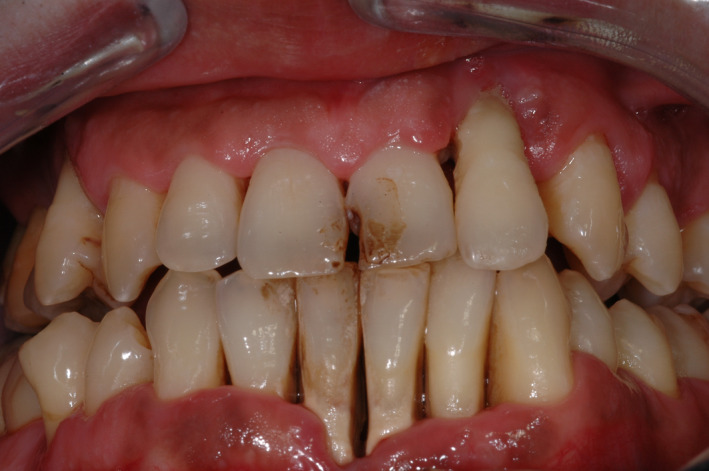

FIGURE 1.

Clinical presentation of a 25‐year‐old Caucasian male patient (cannabis user) with generalized Stage IV, Grade C periodontitis

The deeper inhalation and prolonged contact and absorption time associated with cannabis smoking suggests that it may contribute to the etiology of periodontal disease (Figures 1 and 2).